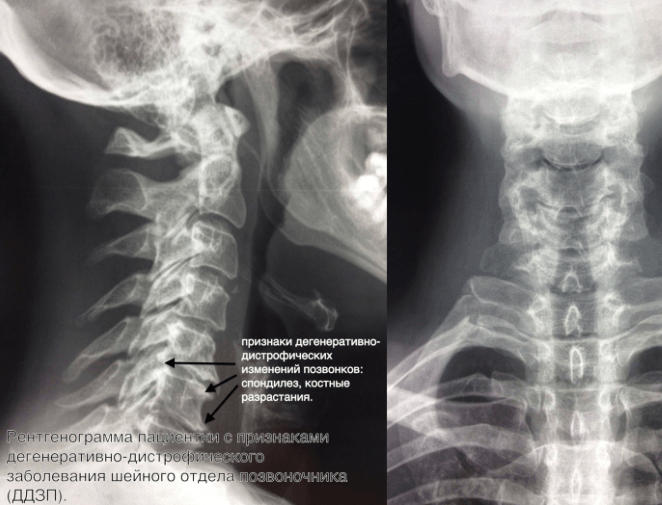

Рентген поясницы: анатомические особенности и медицинские исследования